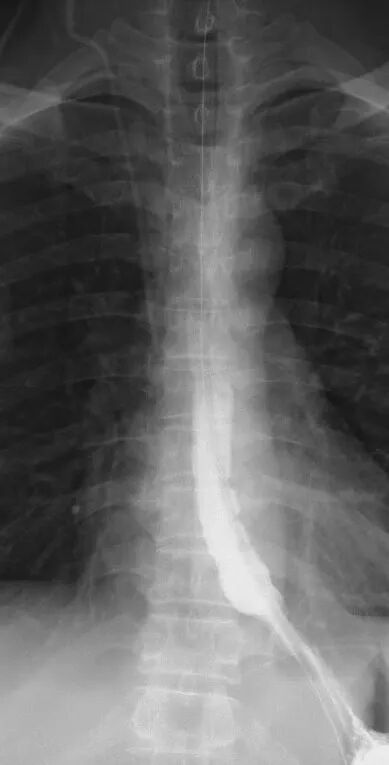

术后复查上消化道造影提示胃底恢复至膈肌平面以下,食管-胃结合部通畅

历时约3小时,出血量不足30ml,手术顺利结束。术后6小时,雷先生即可下床活动。在上消化道造影证实胃食管结合部通畅及造影剂无外溢之后,48小时恢复流质饮食。困扰他多年的反酸、烧心、呃逆等症状显著缓解,制酸药也顺利停用。

门诊随访至今未见症状复发。